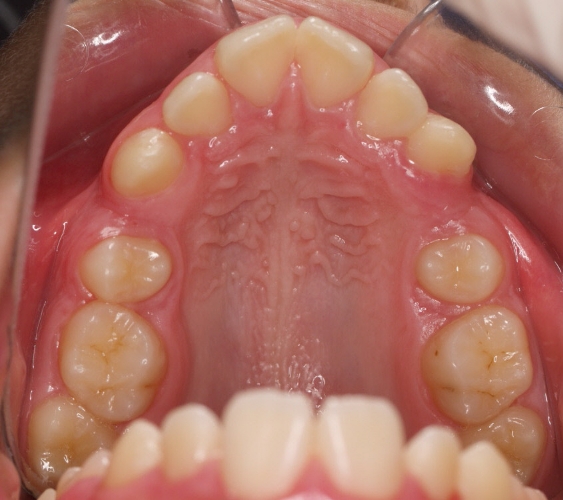

El paciente M.C. acude a nuestra consulta por:

– Apiñamiento importante

– Perfil convexo

– Forma arcada estrecha

-sobremordida

Con lo que decide realizarse un tratamiento de ortodoncia de duración de 26 meses con brackets smartclip 022 de acero.

Fotos antes tratamiento: